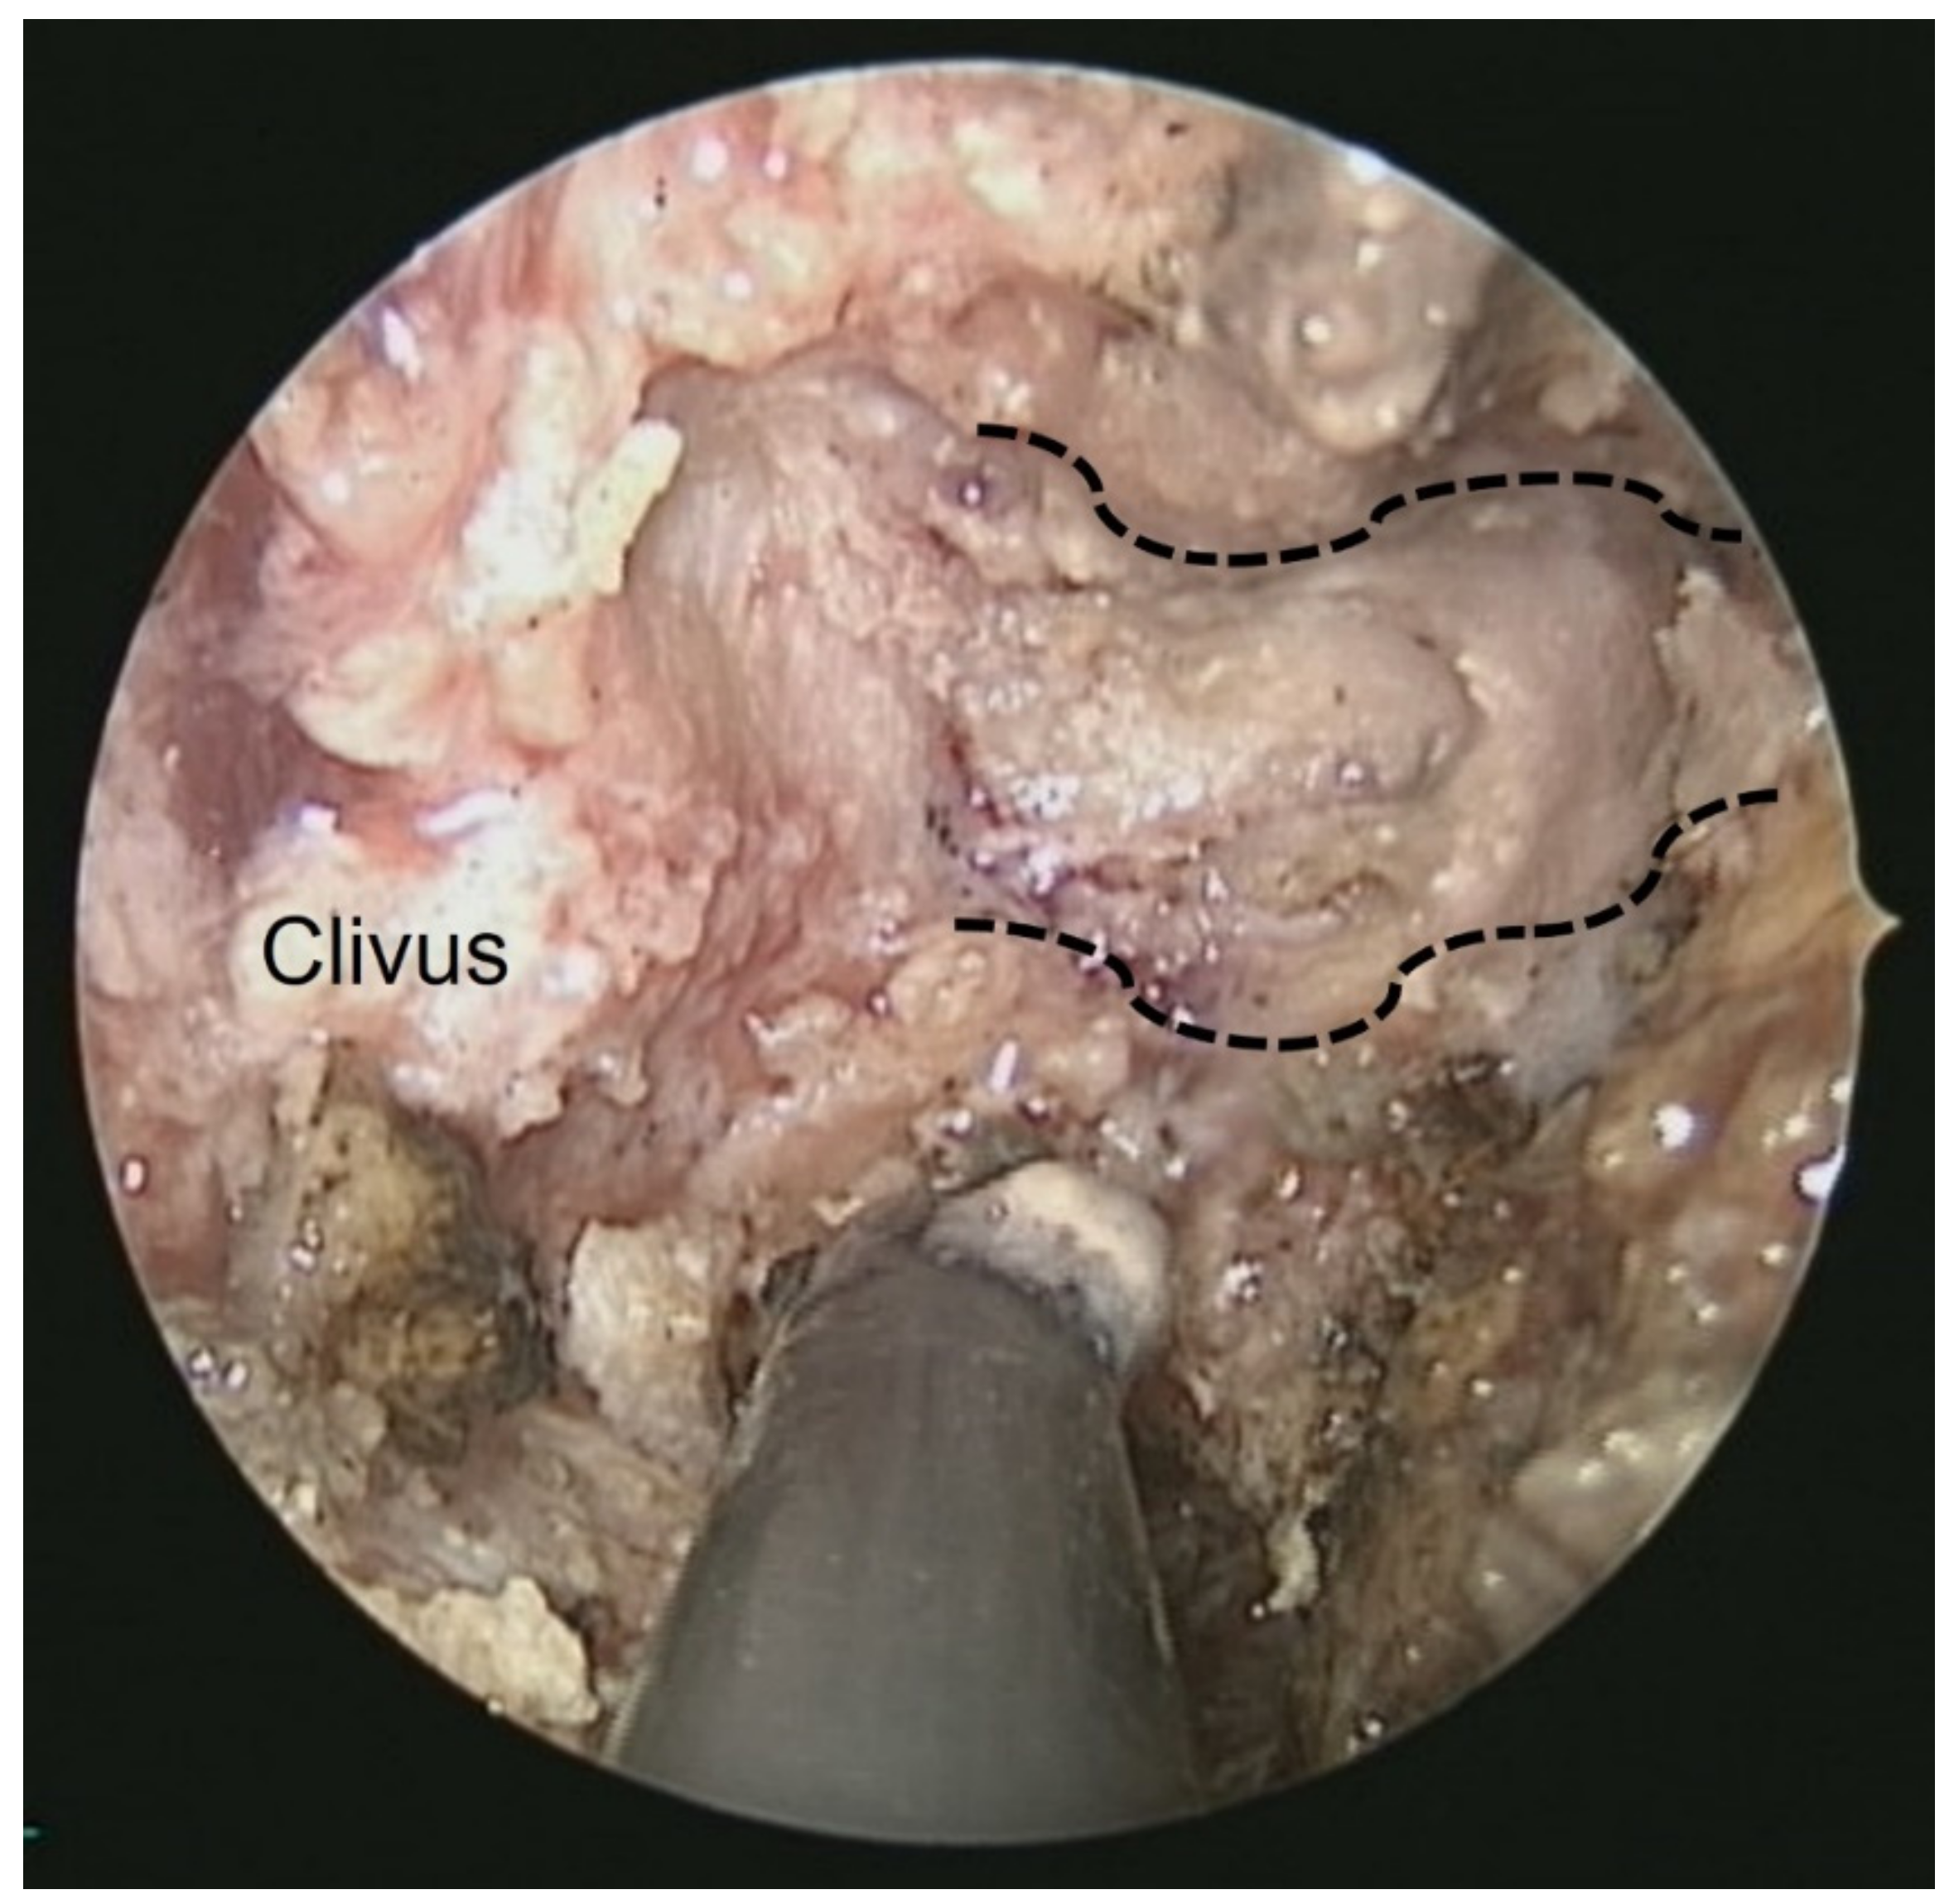

| Present case | Huang et al. | 48M | Dysphagia, hoarseness, tongue atrophy | JF, Clivus, HC, CA | IX, X, XII | T1 iso T2 hypo | + | nil | Endoscopic decompression surgery + prednisolone (10 mg/day for 100 days, oral) | 3 y |